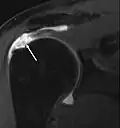

MRT einer kompletten Ruptur -

Magnetresonanzarthrographie

Die Magnetresonanztomographie, gegebenenfalls mit intraartikulärer (direkt in das Gelenk verabreichter) Kontrastmittelgabe („MR-Arthrographie“), zeigt sehr genau zerstörte Strukturen auf und gehört mittlerweile zu den Standarduntersuchungen bei Schultergelenksläsionen.[14]